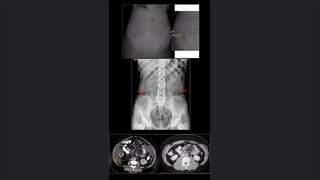

Otros signos del Riñón

Riñón anillo, bordes y halos